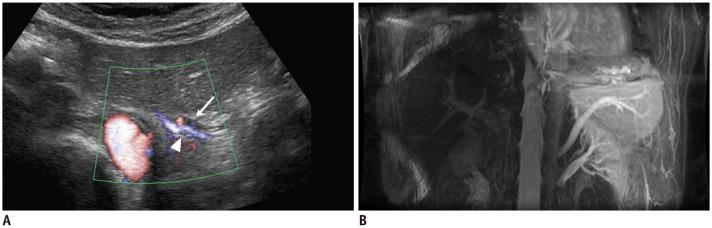

Respiratory-gated three-dimensional balanced steady-state free-precession scans were conducted on 31 healthy subjects using two methods (A and B) for visualizing the LGV with hepatopetal flow. In method A, two time-spatial labeling inversion pulses (Time-SLIP) were placed on the whole abdomen and the area from the gastric fornix to the upper body, excluding the LGV area. In method B, nonselective inversion recovery pulse was used and one Time-SLIP was placed on the esophagogastric junction. The detectability and consistency of LGV were evaluated using the two methods and ultrasonography (US).

Left gastric veins by method A, B, and US were detected in 30 (97%), 24 (77%), and 23 (74%) subjects, respectively. LGV flow by US was hepatopetal in 22 subjects and stagnant in one subject. All hepatopetal LGVs by US coincided with the visualized vessels in both methods. One subject with non-visualized LGV in method A showed stagnant LGV by US.

Hepatopetal LGV could be selectively visualized by method A in healthy subjects.